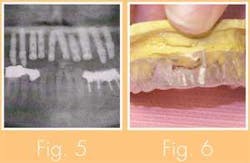

Stage II-Biolock silhouette implants were placed in positions 6 through 11. A new temporary was made and cemented on the posterior abutments now placed on 4, 5, 12, and 13 (see Figs. 5 and 6).